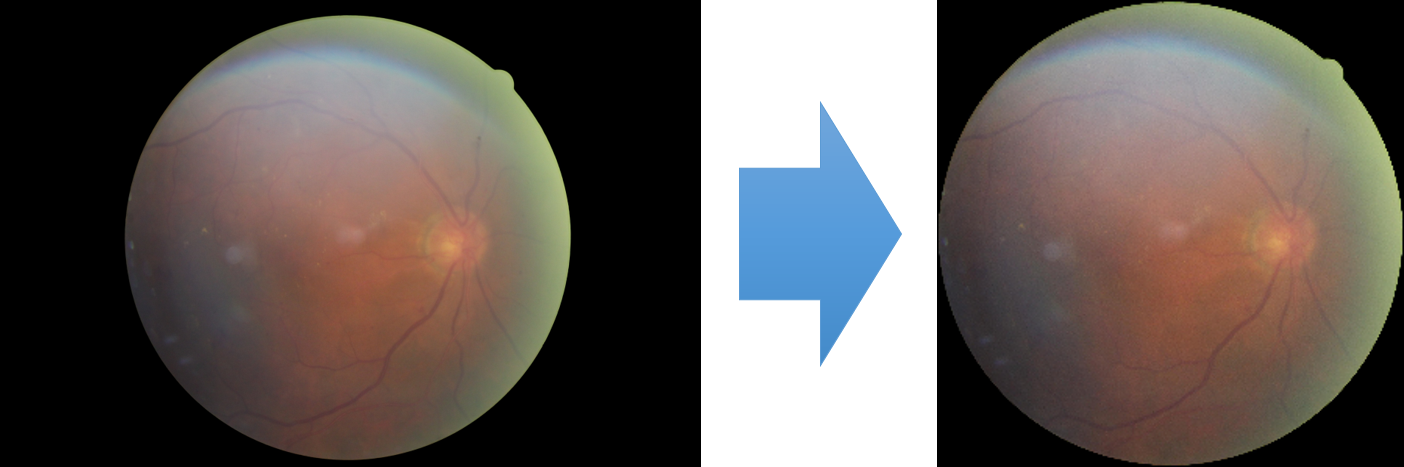

To model how different classifiers will respond to a given input , we assume that the prediction from classifier is sampled from a beta distribution that is characterized by two parameters by and . We further assume that is fixed to the same constant value for all ’s. Under this assumption, each input can be described by ( can be calculated since is fixed), easing further analysis. The Severity Level (SL) of the case represented by image can be characterized by the parameter . The larger the value of , the more severe the case of is. When and are close, the case is ambiguous as the distribution shifts towards being symmetric (i.e. signifying much disagreement among classifiers) rather than being one-sided (i.e. consensus among classifiers that is negative or positive). We provide a set of examples in Figure 2 and also Figure S.8 in the supplementary materials showing how the beta distribution can be used to capture diverse predictions given by an ensemble learner.

We conducted a case study on diagnosing diabetic retinopathy with ensembles of DL models. For benchmarking the performance of our ensemble-based solutions under the scheme described in Sec.3.3, we used two popular collections of diabetic retinopathy image data, the Kaggle Diabetic Retinopathy dataset [22] (hereafter referred to as “Kaggle-DR”) and the Messidor-2 dataset [23], each respectively consisting of and high resolution images. Diabetic retinopathy is graded into five SLs, as displayed in Figure 2. Following the problem setup used in previous papers [24], we trained models to distinguish the referable (SL2-4) cases from the non-referable ones (SL0 & SL1) (see Section B.1 for more detailed descriptions). We also tested our trained ensemble models on two o.o.d. image datasets (ImageNet [25] and CIFAR-10 [26]) to examine their capabilities of identifying o.o.d. inputs (see Section B in the supplementary materials).

The Kaggle-DR dataset comprises high resolution images. The presence of diabetic retinopathy is rated into five different SLs: no-DR (SL0), mild (SL1), moderate (SL2), severe (SL3), and proliferate (SL4), as illustrated in Figure 2. We divided the Kaggle-DR dataset into a development set and a test set, which respectively consisted of and images. The data in the development set were used to train and validate our Deep Learning (DL) models. The Messidor-2 dataset [38] that consisted of images was also used in our experiment as an additional dataset to test the true generalization performance of the models trained on the Kaggle-DR dataset. Images in Messidor-2 dataset were graded into the five SLs as in the Kaggle-DR dataset. Figure S.1 provides an illustration of the datasets used in our experiments.

The image data used in our experiment were all unified into square-shaped images with resolutions or in our preprocessing procedures. For training each neural network model, only images of the same resolution were used. The original images came with either of the two forms as exemplified in Figure S.2. In the first form (Figure 2(a)), the entire fundus was visible in the image. We cropped the image such that the fundus was tightly fitted inside the square. In the second form of input images shown in Figure 2(b), part of the fundus was not visible. We padded blank strips to make the image square-shaped and in a unified resolution. See the provided code for further details.